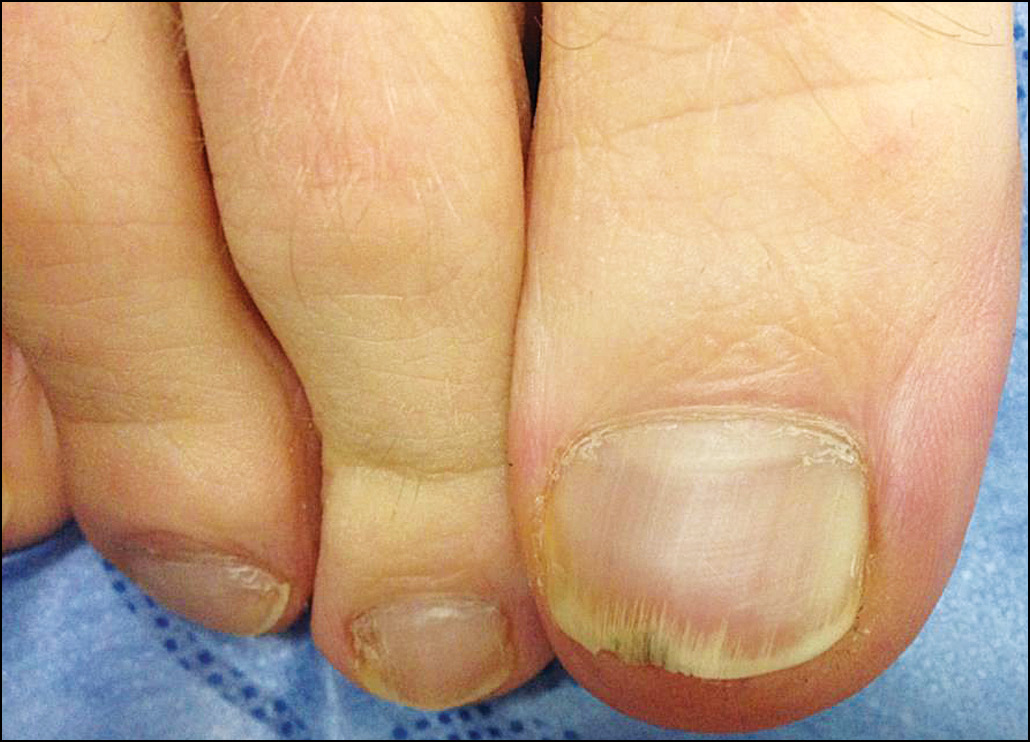

Рис. 10. Больная Е., 78 лет. Гипертрофическая форма руброфитии ногтей.